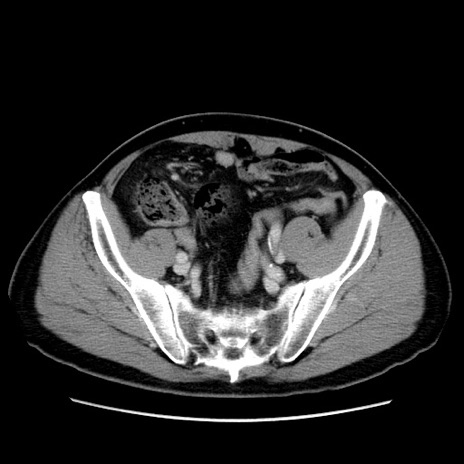

症例34(横断像)

【症例】60歳代 男性

【主訴】右鼠径部膨隆

【現病歴】1年程前より右鼠径部膨隆あり。自己にて還納可能だったため放置していた。3時間前より右鼠径部の脱出を認め、還納困難となり受診。

【既往歴】高血圧

【身体所見】右鼠径部に小児頭大の膨隆あり。弾性硬であり、用手還納は困難。左鼠径部にも膨隆を認める。脱出はなし。